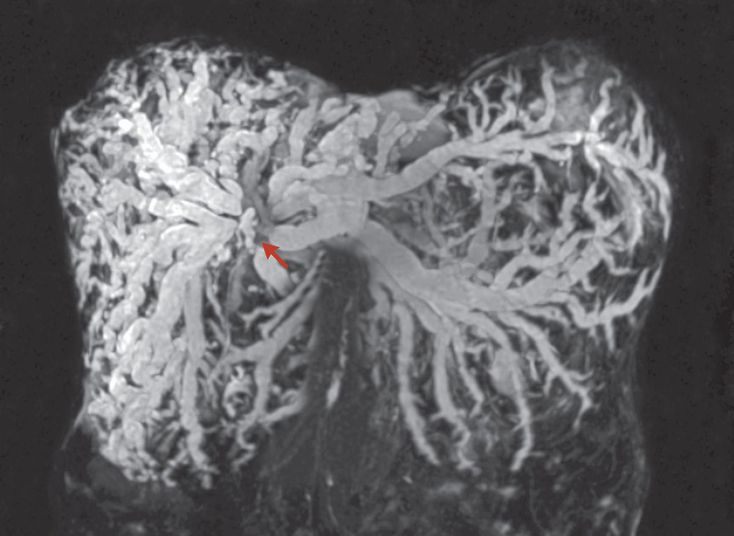

A 72-year-old woman presented to the hospital with abdominal pain, jaundice, and pruritus. She reported a 6-kg weight loss over the previous 2 months. Laboratory studies showed a direct bilirubin level of 14.3 mg per deciliter (normal range, 0.1 to 0.3), an alkaline phosphatase level of 223 U per liter, an aspartate aminotransferase level of 55 U per liter, and an alanine aminotransferase level of 56 U per liter. Magnetic resonance imaging of the abdomen revealed marked intrahepatic biliary ductal dilatation, with tapering and cutoff near the hilum (arrow). A hepatic hilar mass with vessel involvement was also visualized (not shown). The imaging was consistent with a diagnosis of hilar cholangiocarcinoma, or Klatskin’s tumor. She underwent percutaneous transhepatic cholangiography with biliary drainage, and a biopsy specimen was obtained from the hilar mass. Histopathological evaluation confirmed the diagnosis of cholangiocarcinoma. Lung metastases were also noted. Given a number of considerations, including involvement of both the hepatic artery and the portal vein, the tumor was not considered to be resectable. In addition to biliary drainage, supportive palliative care was pursued.